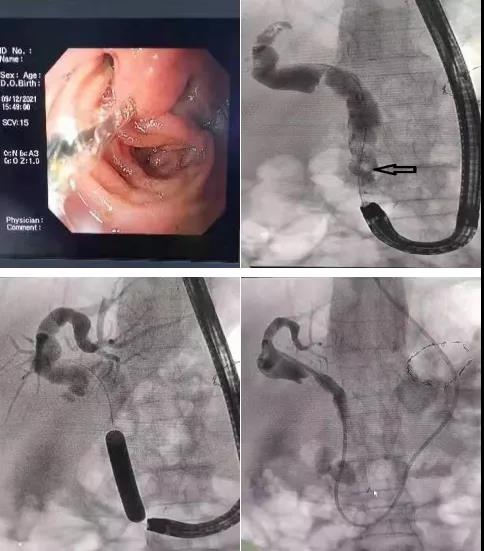

近日,消化內(nèi)二科成功開展首例畢Ⅱ式胃大部切除術(shù)后復發(fā)難治性膽總管結(jié)石的ERCP取石手術(shù)。

患者81歲高齡女性,既往胃大部切除畢Ⅱ式吻合術(shù)后30余年,因發(fā)熱、腹痛入院,診斷為膽總管結(jié)石、急性梗阻性化膿性膽管炎。患者存在高齡、感染性休克等情況,病情復雜危重,蓋偉主任立即爭分奪秒組織科內(nèi)專家仔細分析討論病情,決定首選ERCP取石術(shù)。

與家屬充分溝通后,蓋偉主任和田宗彪主治醫(yī)師開始內(nèi)鏡下取石術(shù),交替使用十二指腸鏡和胃鏡找到改道后的十二指腸乳頭,通過胃鏡完成插管、乳頭擴張成型、取石及鼻膽管置入,順利完成手術(shù)。術(shù)后,患者腹痛、發(fā)熱、黃疸等癥狀消失,三天后順利出院。